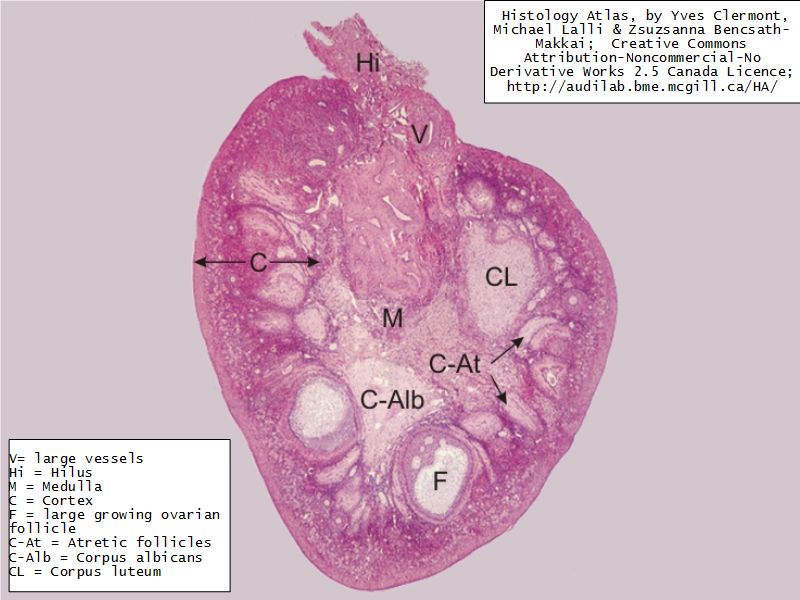

Ovaries

Slide 24

Section of the ovary

1. Outer covering. 1'. Attached border. 2. Central stroma. 3. Peripheral stroma. 4. Bloodvessels. 5. Vesicular follicles in their earliest stage. 6, 7, 8. More advanced follicles. 9. An almost mature follicle. 9'. Follicle from which the ovum has escaped. 10. Corpus luteum.

Ovary

- Capsule covered by modification of peritoneum

- Called germinal epithelium

- Simple squamous/cuboidal

- Subdivided

- Not clearly defined

- Cortex - contains ovarian follicles

- Medulla - vascular

Germinal epithelium

- Misnomer

- NOT source of primary follicles

- Cover capsule

- Simple squamous/cuboidal epithelium

Cortex

- Tunica albuginea

- Irregular dense CT capsule

- Follicles in various phases

- Stroma containing follicles

Stroma

- Highly cellular loose CT

- Fibroblasts

- Elastic & collagen fibres

- Form layers around follicles

Medulla

- Blood vessels

- Hilus cells

- Stroma

Blood vessels

- Enter medulla at hilus

- Supply the cortex

- Epithelioid cells clump around blood vessels

Epithelioid cells

- Located in hilus

- Also called hilus cells

- Clump around blood vessels

- ≈ Leydig cells

- Probably produces androgens